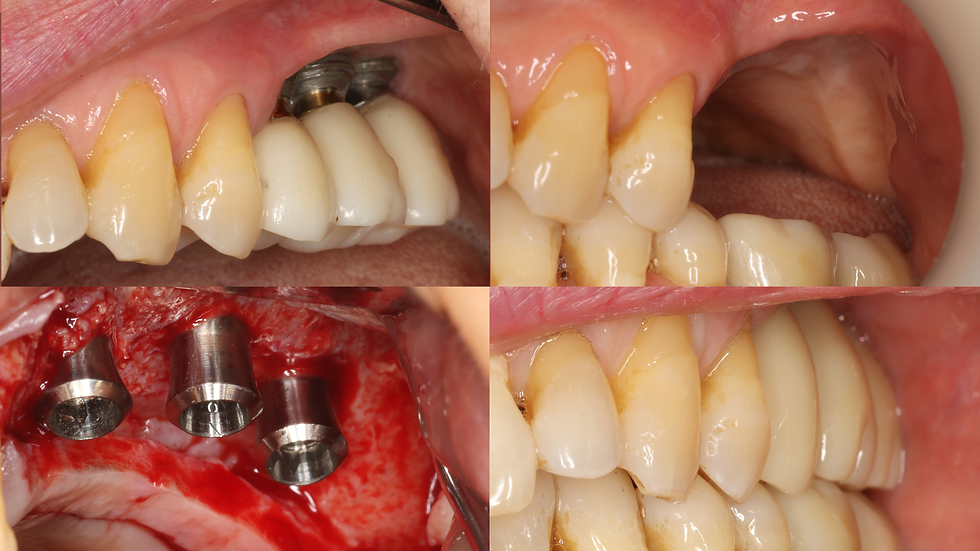

6 months follow-up after restoration

6 months follow-up after restoration, where we can see the new bone regeneration from 3 mm to 6.9 mm width

Conclusion Even with a soft tissue complication, the GBR is a predictable procedure if we know how to resolve it.